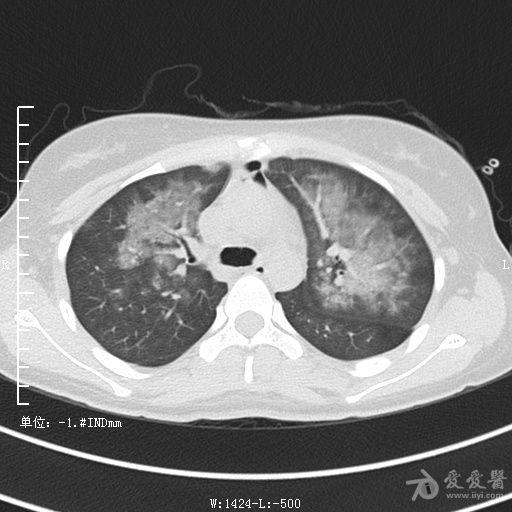

典型支气管扩张及肺水肿CT片

典型支气管扩张肺水肿